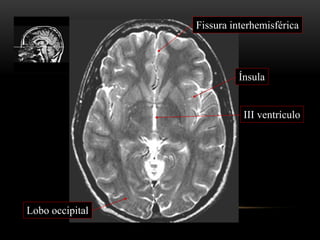

III ventrículo

Lobo occipital

Fissura interhemisférica

Ínsula